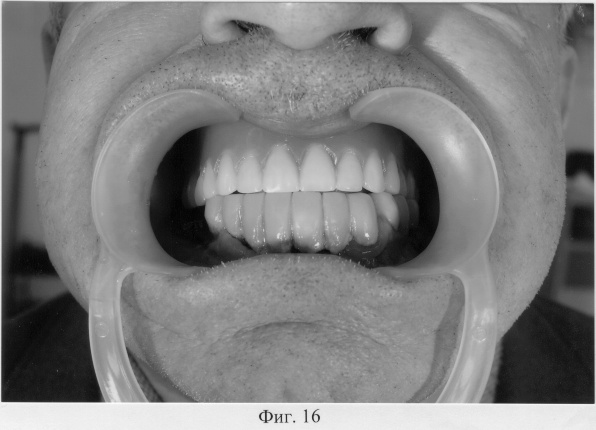

На фиг.16 – полный съемный зубной протез верхней челюсти в полости рта больного Т. в состоянии центральной окклюзии.